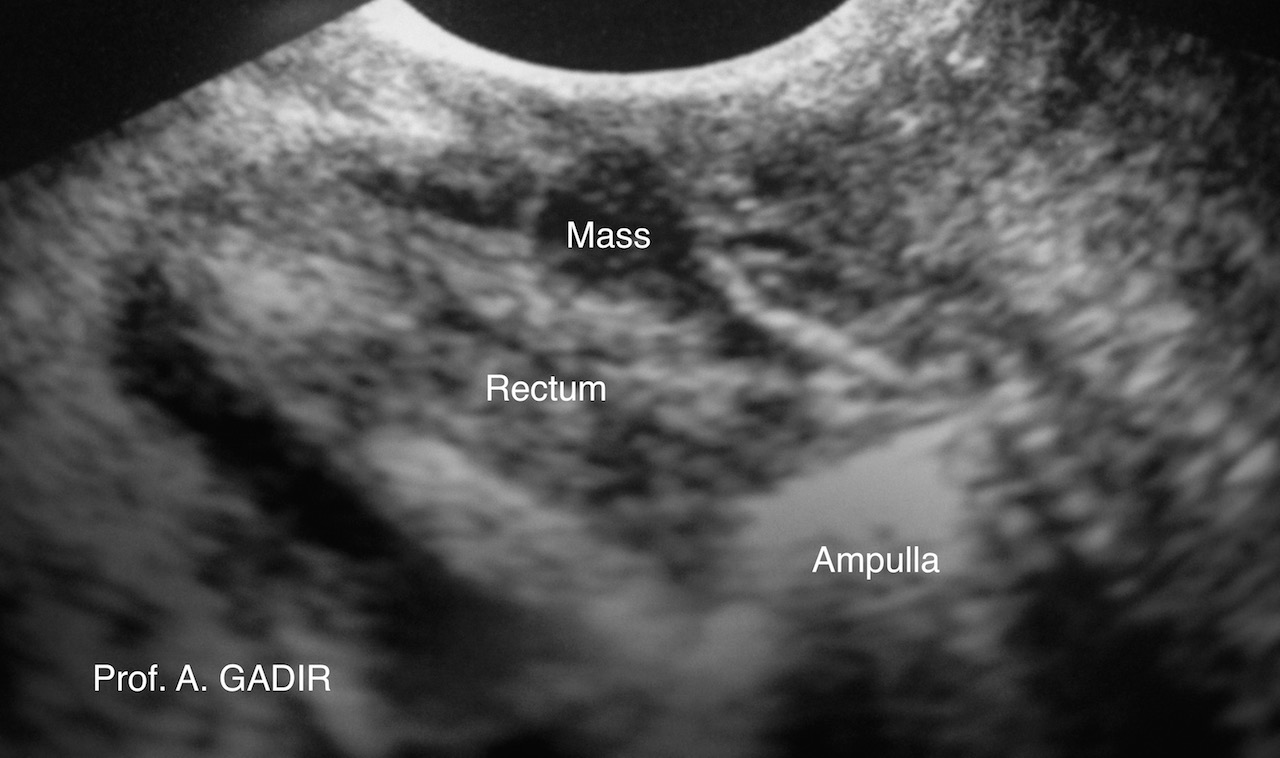

Endometrioma_rectum_anotated

A slightly oblique Longitudinal view of the anal canal and rectum up to

the rectal ampulla showing a circular mass on the front wall of the rectum.

This proved to be endometriotic nodule. The patient presented with

dyspareunia, as well as tenismus and diarrhoea, mainly during

menstruation